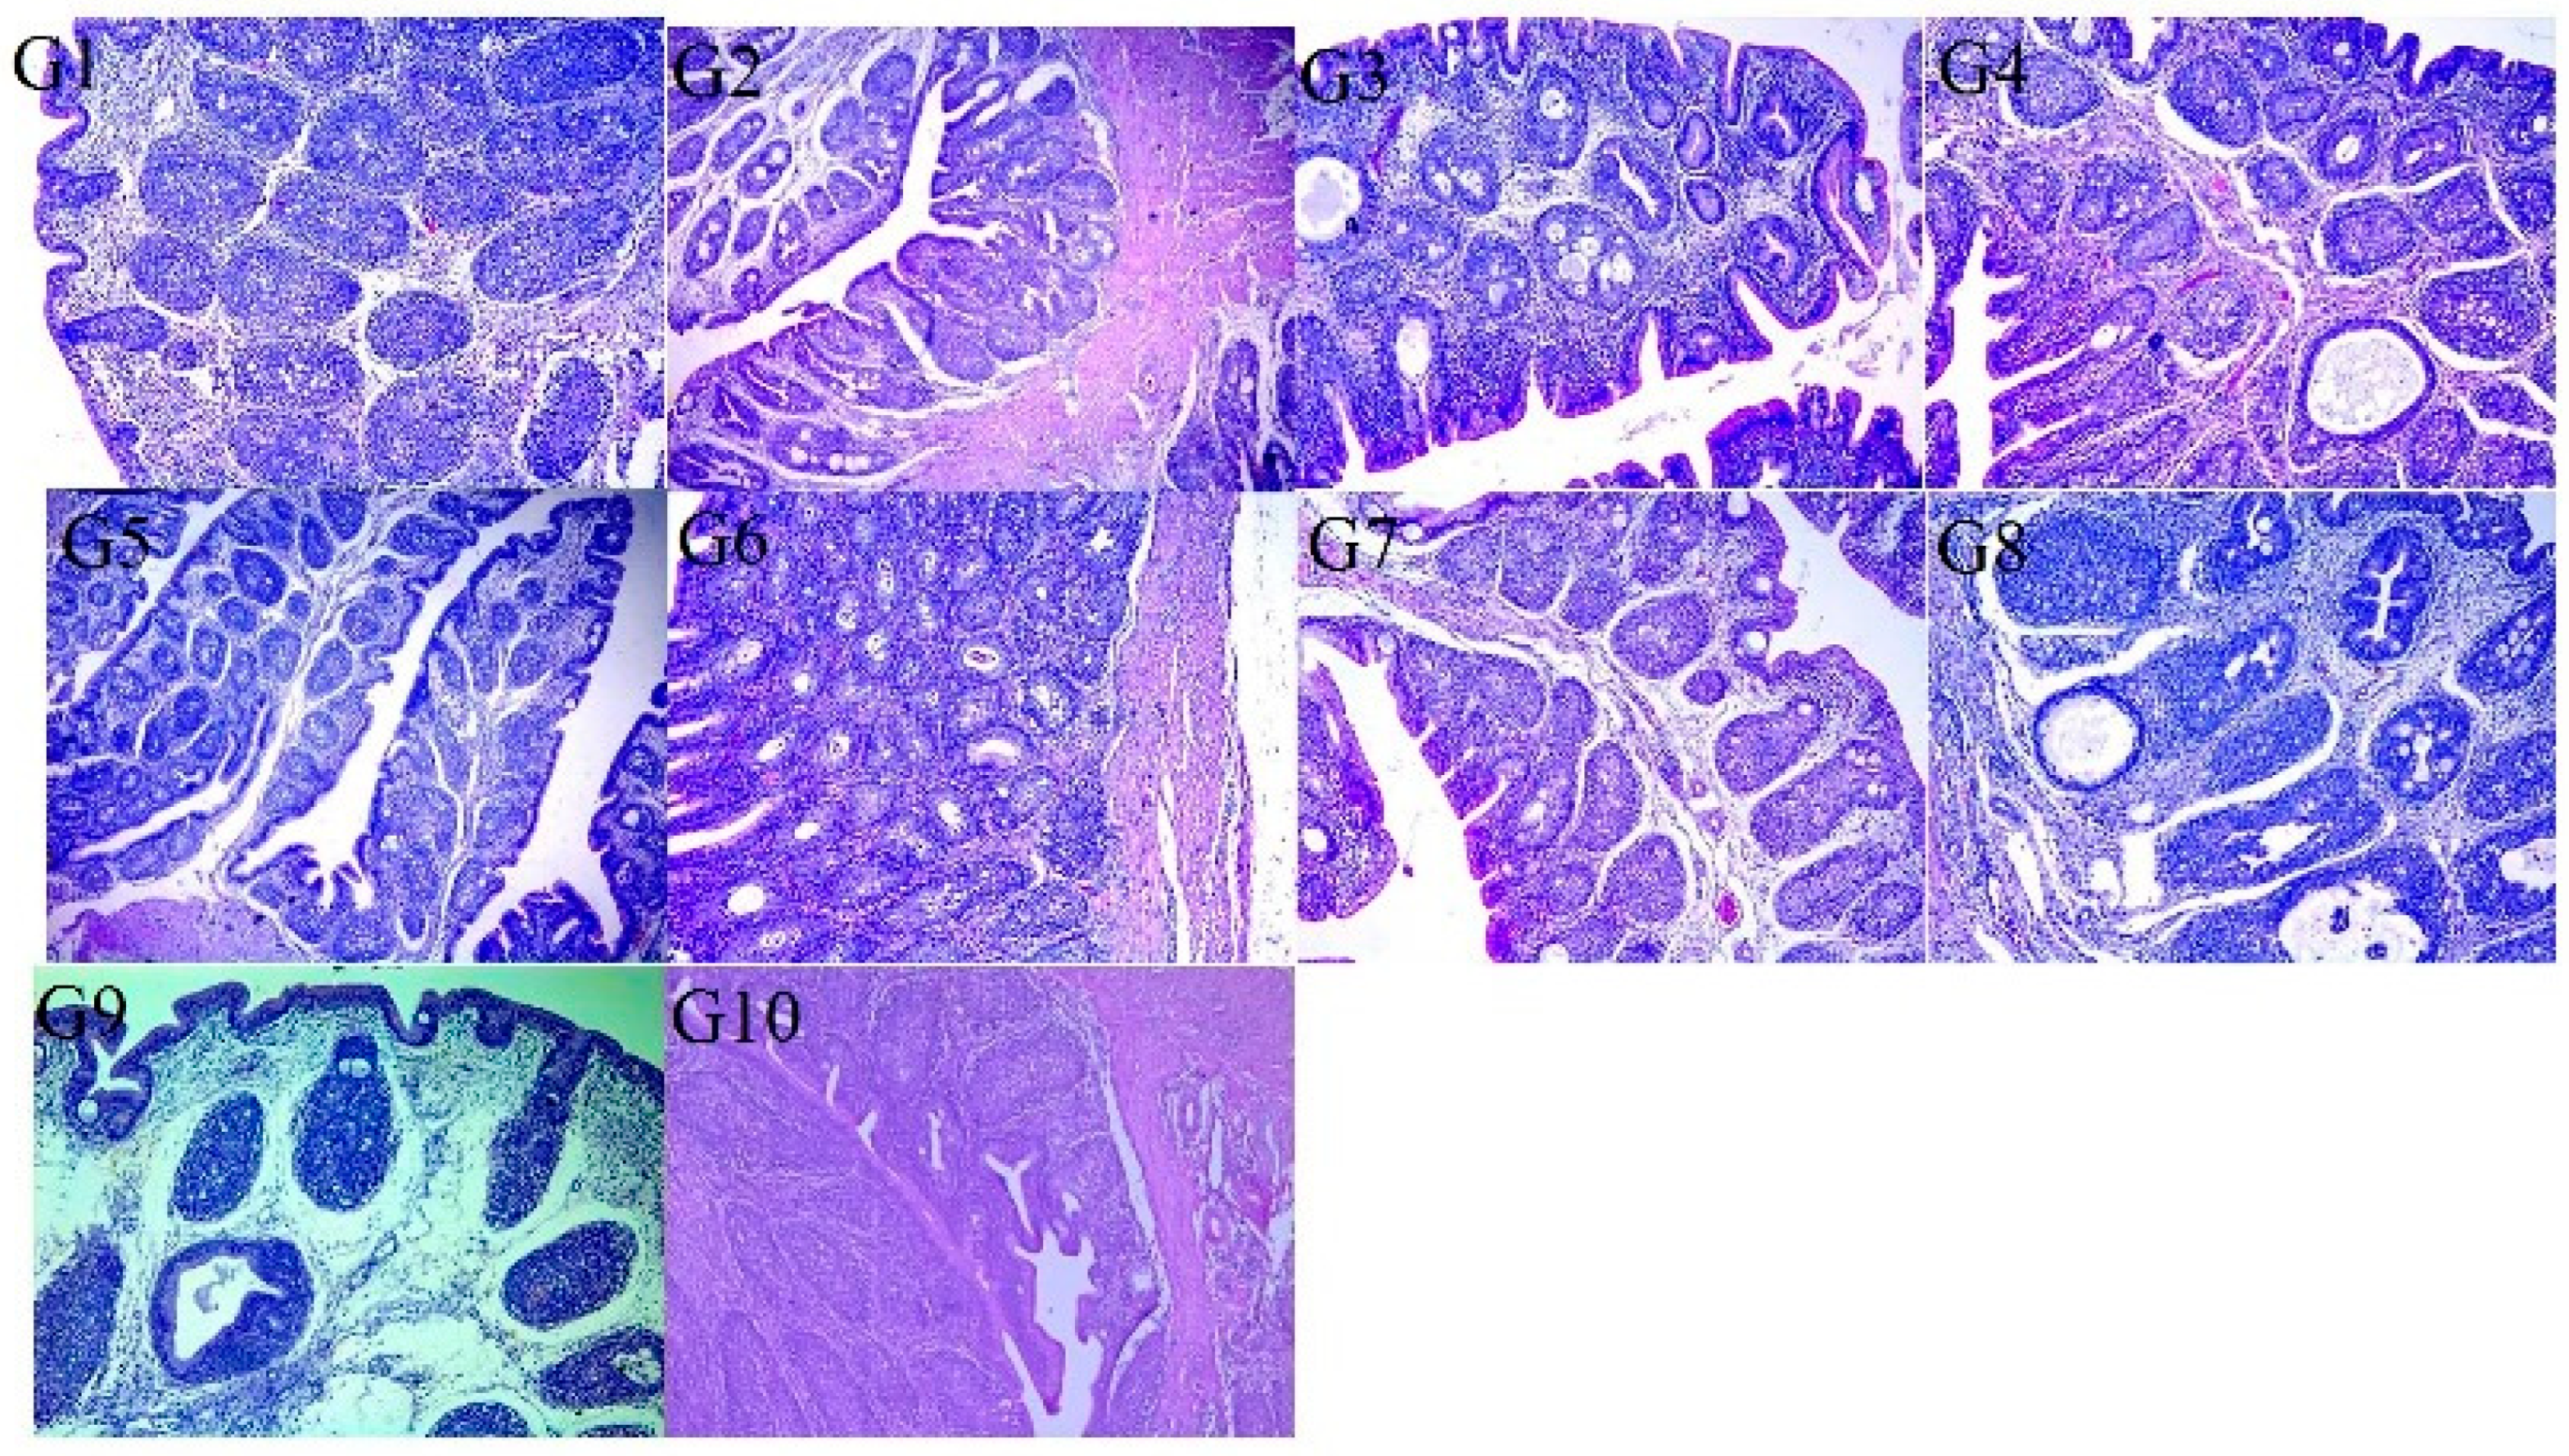

3.5. Histopathological Examination

| Score | Trachea (% of Wall Affected) |

|---|---|

| 0 | No change |

| 1 | 25% |

| 2 | 26–50% |

| 3 | 51–75% |

| 4 | 76–100% |